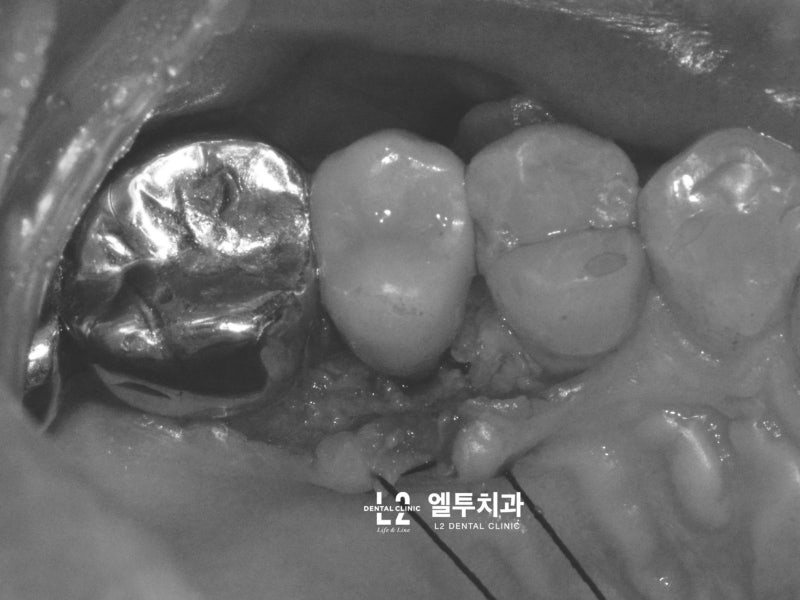

큰어금니와 작은어금니의 갈라진 치아 모습에는 차이가 있는데, 큰어금니의 갈라진 치아는 대부분 “기능적 팁” 쪽, 즉 치아에서 더 큰 스트레스를 받는 부분에서 발생합니다. (아래 포스팅 참조) https://blog.naver.com/sunnyflow/222654941394 Q-ray 촬영으로 어금니 크랙(균열)을 미리 확인하고 대비할 수 있습니다. 닥터&치주과의사 최순호 입니다 오늘은 어금니 중문으로 가는데… blog.naver.com 물론 기능교두의 기능교두는 작은 어금니에도 크랙이 생기는 경우가 많은데, 치아가 부러지는 원인. 음식을 씹을 때 위아래로 씹지 말고 나란히 씹는다. 이것을 치과 용어로 “Lateral Guidance”라고 하는데 위 사진에서 색종이(교합용지)를 찍으면 치아에 가해지는 힘이 화살표 방향으로 퍼지는 것을 볼 수 있습니다. 다시 케이스로 돌아가서 왼쪽 위 어금니가 이전에 근관치료와 크라운 치료를 받았고 씹을 때 불편하다고 하셨습니다. X-레이를 보면 치근/크라운 치료를 받은 어금니 주변에 어두운 그림자가 보일 것입니다. 뼈가 녹으면서 “J자 모양”이 되고 X-레이에서 보이는 이러한 방사선학적 변화는 종종 치아의 깊은 층에 균열이 있음을 나타냅니다(크라운 뿌리 균열, 뿌리 균열 = 치근. 갈라진 치아). 측방 구강 내부에서 송곳니가 곧게 연마되는 것과 같이 측면 안내 중에 치아가 강한 측면 힘을 받는 것으로 추론할 수 있습니다. 이 힘이 계속되면서 작은 어금니 부위에도 깊은 균열이 발생했다. 이 정도까지 치아 사이의 간격이 벌어지면 치과에서 치료할 방법이 없기 때문에 발치 후 임플란트 치료를 권해드립니다. 발치 모습. 화살표가 가리키는 부분을 자세히 보면 치아의 머리 부분에서 시작하여 치근 깊숙이 뻗어나가는 크랙(균열)을 볼 수 있습니다. 입 안의 세균이 미세하게 새는 것은 균열선을 따라서만 진행될 수 있어 잇몸뼈가 재흡수되어 씹을 때 통증이 발생합니다. 임플란트 수술은 발치 당일에 시행하고 일정 기간 치유 후 작은 어금니 부위에 임플란트 크라운을 식립합니다. 이러한 현상을 가진 환자들은 이상한 점을 발견할 수 있는데, 반대측 치아에서도 비슷한 상황을 관찰하는 경우가 매우 흔하다. 반대쪽 소구치를 보면 잇몸뼈가 주변 치아와는 매우 다른 방식으로 흡수되는 것을 볼 수 있습니다. 이 치아 역시 치근 치료와 크라운 치료를 한 치아이기 때문에 치아의 치근쪽에 크랙이 나타난 것으로 의심됩니다. 문제 치아 옆의 작은 어금니도 균열이 의심되는 Q-선 형광 검사에서 관찰되었습니다. 금이 간 치아가 강하게 의심되었지만 어쨌든 심각한 치은 골 흡수가 관찰되었으므로 “진단”+ “치료”의 목적으로 치은 박리를 시행했습니다. (환자분들이 아프지 않을때까지 보관하라고 하셔서 알고 있습니다.) 이렇게 입에 금이 간 치아가 많은 분들은 예방적 크라운 치료를 권해드리고 있습니다. 크라운 치료는 앞니의 단점이 있지만 “치아 보호”가 최우선입니다. 위에서 언급한 2개의 치아 외에도 양쪽 소구치에 크랙이 관찰되어 더 진행하면 바로 발치할 수 있어 환자에게 크라운 치료를 알리고 진행하였다. 너무 늦기 전에… 깨진 치아를 무시하면 종종 손을 사용하지 않고 발치 및 임플란트 치료가 발생할 수 있습니다. https://blog.naver.com/sunnyflow/222413456775 치아가 깨지거나 부러져 부주의로 발치를 하게 된 사례 안녕하세요. L2치과의원장 최순하오 원장입니다. 최근 치과에 다녀온 환자에서… blog.naver.com 바로 씹어도 통증이 없어도… 상당한 크랙이 관찰된다면 예방적 크라운 치료를 고려해보시는 것을 강력히 추천드립니다:) 오늘의 기사가 도착합니다. 끝. 스마트폰에서 위 부분을 터치하시면 다이얼로 전환됩니다.서울시 강남구 봉은사로 469, S-TOWER L2, 4층 치과